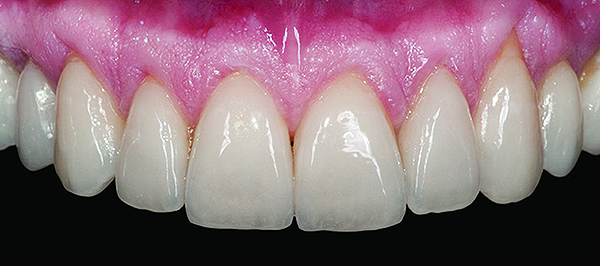

Figure 3 Preoperative, preparation, and final postoperative images of a 2-unit CL-I feldspathic veneer case.

Figure 3

CL-I materials are fabricated by hand (Figure 4); they are the most conservative and generally the most translucent ceramic materials, but they are also the weakest.9,10,18 The material’s high translucency and esthetics create the illusion of natural teeth.9 Powder/liquid porcelain materials are ideal for cases in which significant enamel remains and/or there is healthy tooth structure on the teeth (ie, 50% or more remaining enamel on the tooth, 50% or more of the bonded substrate is enamel, and 70% or more of the margin is in the enamel). Feldspathic porcelain restorations that are bonded to primarily enamel substrates have proven to be highly successful long term.19

Powder/liquid porcelains demonstrate high esthetics and workability, and because they can be layered very thinly and placed directly on the enamel, they are considered the most conservative of the metal-free ceramic classes.10 CL-I porcelains require a thickness of 0.2 mm to 0.3 mm for each shade change.20,21

This class of materials is generally indicated for anterior restorations, but can also be used for the occasional bicuspid and rare molar, providing all parameters are at a very low risk level (Figure 5 and Figure 6).